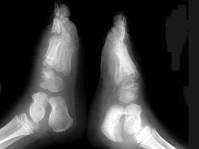

女,5岁,左踝疼痛,结合图像,最可能的诊断是?(?)A.创伤性关节炎B.退行性骨关节病C.神经性关节病D.风湿性关节炎E.痛风

问题 女,5岁,左踝疼痛,结合图像,最可能的诊断是?(?)

选项 A.创伤性关节炎 B.退行性骨关节病 C.神经性关节病 D.风湿性关节炎 E.痛风

答案 C